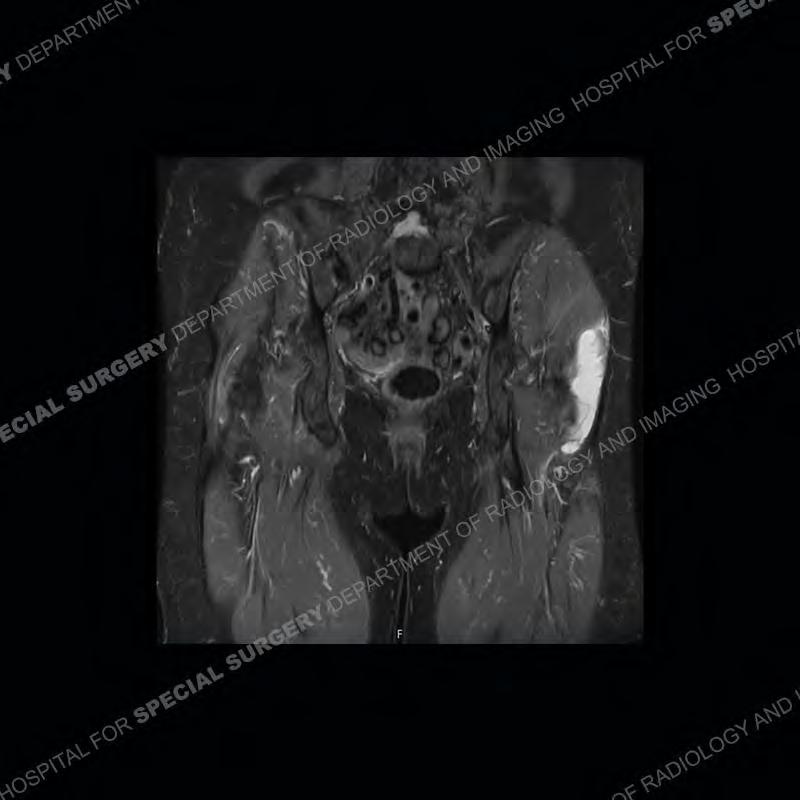

The radiograph is not particularly contributory in this case. The MRI demonstrates markedly abnormal architecture of the gluteus minimus and anterolateral band of the gluteus medius. Portions of the tendons are high signal, portions are highly attenuated, and portions are disrupted. A large, complex fluid collection is present in the adjacent soft tissue.

Diagnosis: Gluteal Tendinosis and Disruption with Complex Trochanteric Bursal Collection

Not as much of a diagnostic dilemma as many of the other cases shown but just a nice example of the pathology seen of the gluteal tendons and a cause of trochanteric pain. Although, frequently thought of in isolation, trochanteric bursitis or bursal thickening is much more commonly a reactive change to underlying pathology of the subjacent gluteal tendons. The gluteus medius is divided into a posterior band and an anterolateral band. Tendinosis and partial tearing very commonly will involve the gluteus minimus and especially the more posterior fibers and then propagate into the anterior lateral band of the gluteus medius. Involvement of the posterior band of the medius is much less common and engenders a marked degree of functional impairment.

The bursae about the greater trochanter can be a little bit confusing especially given the terminology. Trochanteric bursitis is implied to mean the subgluteus maximus bursa which is present deep to the maximus and just lateral/superficial to the trochanter. That is the bursa involved in this case. In this case the complexity of the bursa relates to the tendon tearing with inflammatory change and probably hemorrhage accounting for the complexity. Two other, less frequently involved bursa are also present. The subgluteus medius and subgluteus minimus bursa are found just deep to the named tendons. Although pathology does frequently follow the previously described pattern it is possible to have isolated pathology to either the medius or minimus.